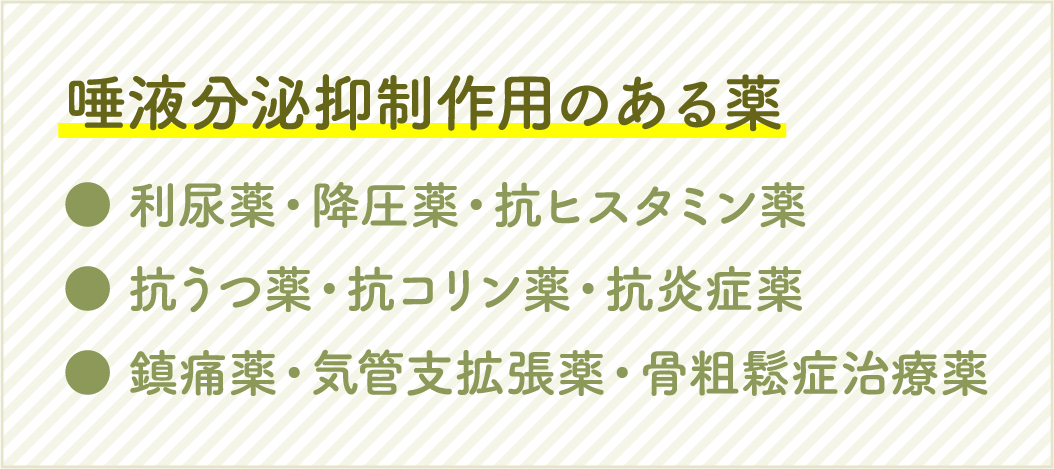

唾液の量は年齢と共に減少することが多いため、高齢になってから一気に虫歯が増えてしまうこともあります。また、唾液が減少してしまう理由としてストレスや体調の変化、薬の副作用などが挙げられます。

これらの薬を服用している方は、歯医者さんにそのことをしっかり伝えることが大切です。